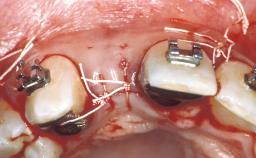

An 18 year-old female patient, a non-smoker,presented in 1999 during orthodontic treatment with a tooth gap in position 22 due to a congenitally missing permanent tooth 22 and a peg-shaped permanent tooth 12. Orthodontic treatment had started four years before, when the patient was 14 years old, to correct a complex situation by maxillary expansion in combination with a bracket treatment. The patient had been referred by the orthodontist for clarification of a possible implant therapy to define the ideal size of the tooth gap at site 22 as well as the necessary root parallelization for implant placement,i.e. final minor orthodontic corrections to create an ideal situation for implant placement.